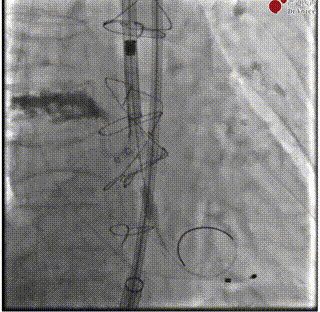

释放前造影确定位置和深度

完全释放

最后造影

术后超声

闭合血管入路,完成手术。本例难点在于SAVR术后结构性瓣膜衰败导致主动脉瓣反流,原外科瓣膜未见钙化,术前经充分沟通,确定植入深度于瓣架第一节点与第二节点间,保证瓣架底部在外科瓣膜环上具有足够锚定力。术中,瓣架完全释放前小弯侧深度稍大于大弯侧,微量PVL,在最终时提示术者对递送系统轻微施加推力,释放后两侧深度达到平衡,PVL消失,平均压差2mmHg,舒张压即刻恢复正常。